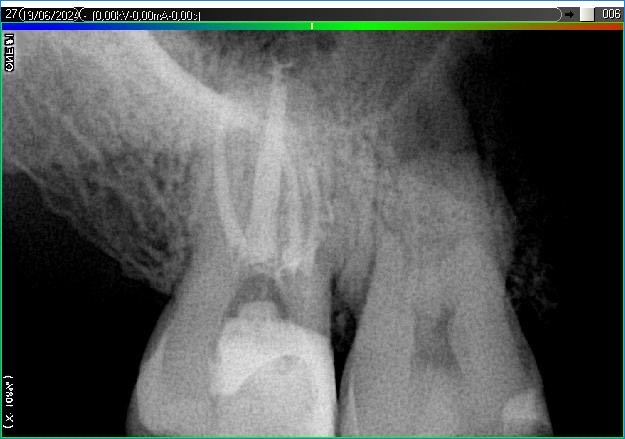

Вилучення інструменту з каналів зуба